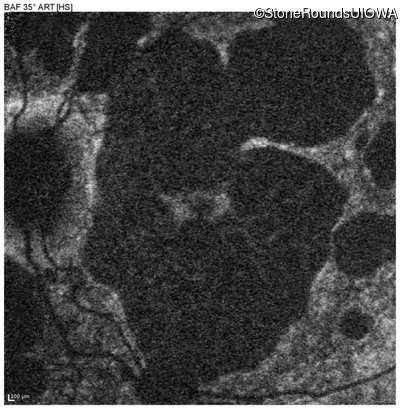

Blue Autofluorescence - Right - 20/40 -2

Exemplar

Blue Autofluorescence - Left - 20/40 +1